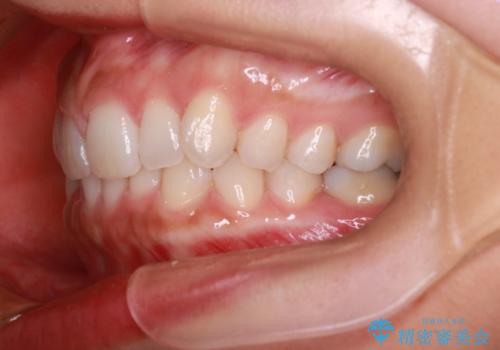

【インビザライン】前歯のねじれを治したい

- 前歯のガタガタを主訴に来院されました。

叢生の量は軽度でしたが臼歯の遠心移動を行い、インビザラインにて治療をしました。

叢生の改善に必要なスペースは遠心移動やIPRで作ることが可能です。今回は遠心移動をメインにスペースを作って叢生の改善を行いました。